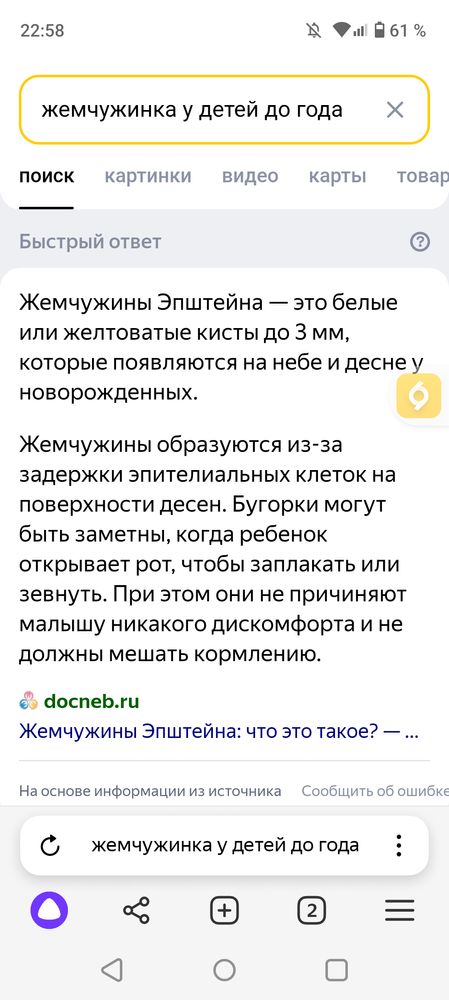

Девочки, подскажите, что это? Выделила красным.

Уже около месяца такая штука, только становится больше, белее, что ли, сильнее видно, это зуб так лезет ? Хотя у других зубов так не было.